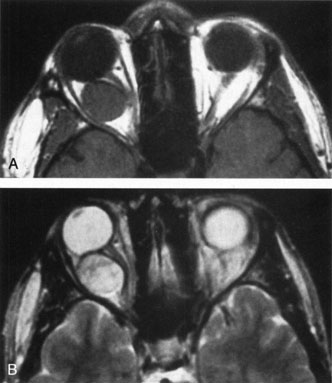

There are no pathognomonic ultrasonography, CT, or MRI findings. A-scan ultrasonography shows well-delineated regular structures with low internal reflectivity and minimal attenuation owing to the congested pools of blood in the dilated veins. Doppler demonstrates flow within the lesion.58 Computed tomography may show abnormally dilated, irregular veins with uniform contrast enhancement or, when there has been hemorrhage, multilobular lesions.58 As the VFM may not be visualized when collapsed, direct coronal scans should be obtained in the prone position or during the Valsalva maneuver to distend the lesions (Fig. 14). Spiral CT with a single breath-holding technique may be useful in confirming an increase in size of the lesion during the Valsalva maneuver.104 The majority of venous malformations typically occupy the superomedial orbit in the area of the superior ophthalmic vein, followed by the inferolateral quadrant.95,104 In their study of 158 patients with NFM and VFM, Wright and colleagues found 45% with phleboliths.95 Enlargement of the affected orbit also may be seen.95 Obtaining MRI scans before and during a Valsalva maneuver may show distensibility, and uniform enhancement occurs.58 Venography is seldom used now because of the availability of other imaging modalities. Carotid angiography may demonstrate the VFM and can detect venous enlargement consequent to arteriovenous shunting.

Fig. 14. Orbital venous flow malformation. Axial computed tomography scan showing an ill-defined, dense, inhomogeneous orbital lesion with the patient in a supine position (A). Note the phlebolith, which indicates venous stagnation. As the venous flow malformation distends with the patient in the prone position, the lesion enlarges (B). (Courtesy of Dr. John V. Linberg, University of West Virginia, Morgantown, WV)